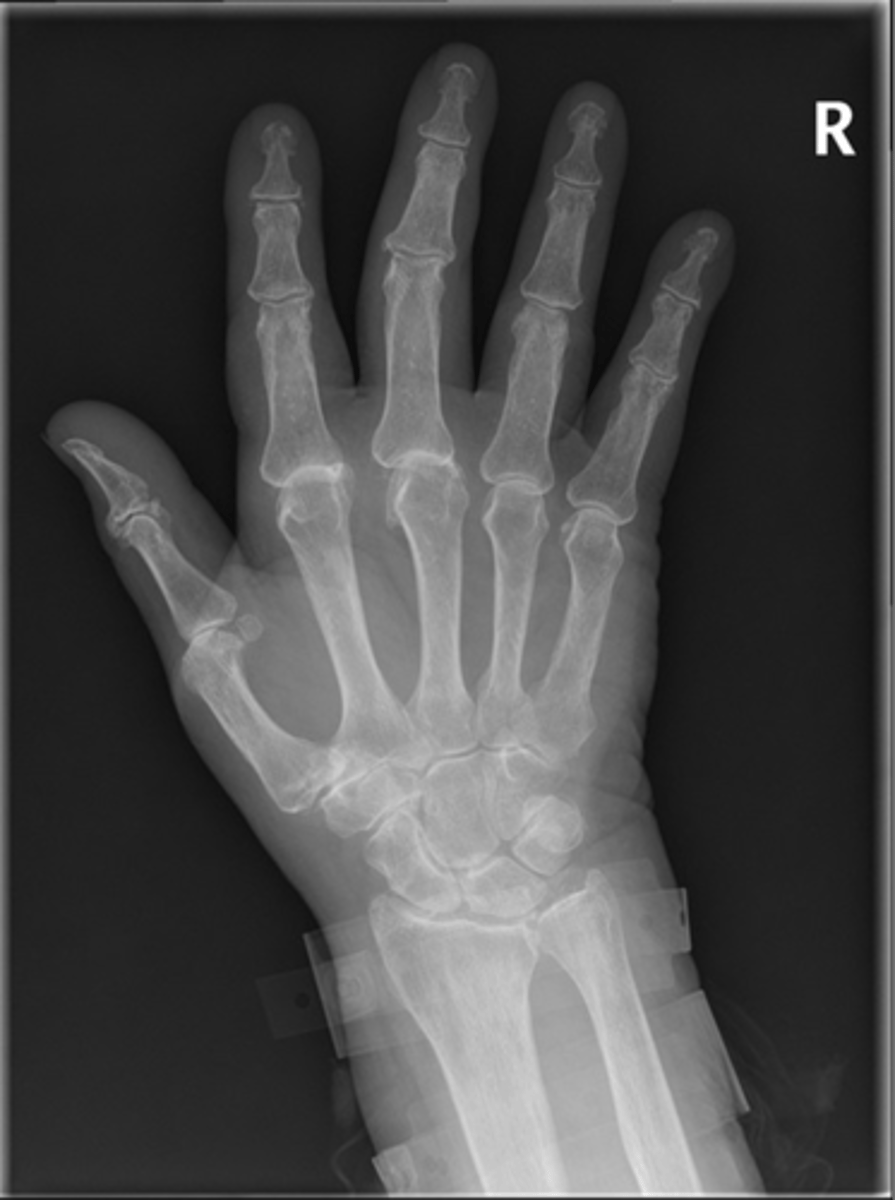

- Dense soft tissue tophi (swelling)

- Bone erosions

- Overhanging margin sign

- Secondary degeneration

- 1st MTP MC joint

State the radiographic findings of gout

- Soft tissue swelling

- Chondrocalcinosis

- Severe degeneration

- Pyrophosphate arthropathy

- Articular destruction

- SLAC wrist (scapholunate advanced collapse)

State the radiographic findings of calcium pyrophosphate dihydrate crystal deposition disease (CCPD)